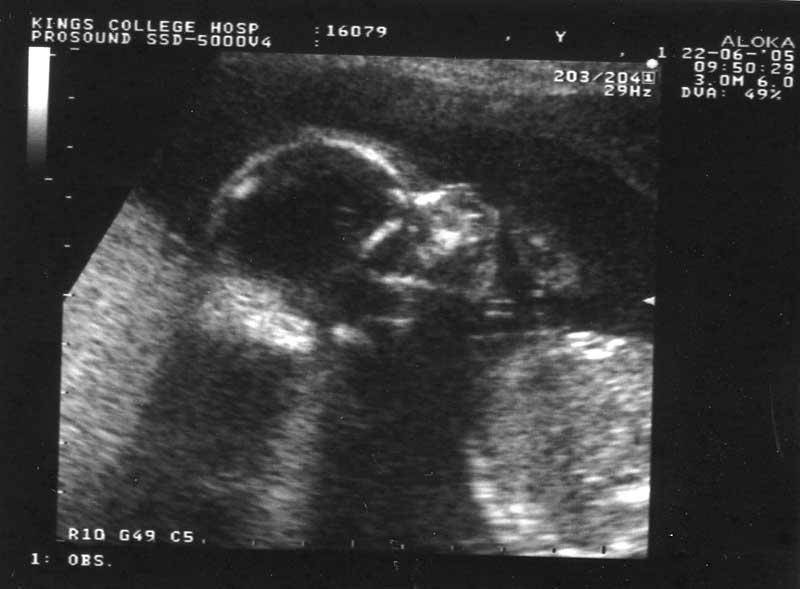

second scan

first cute pic